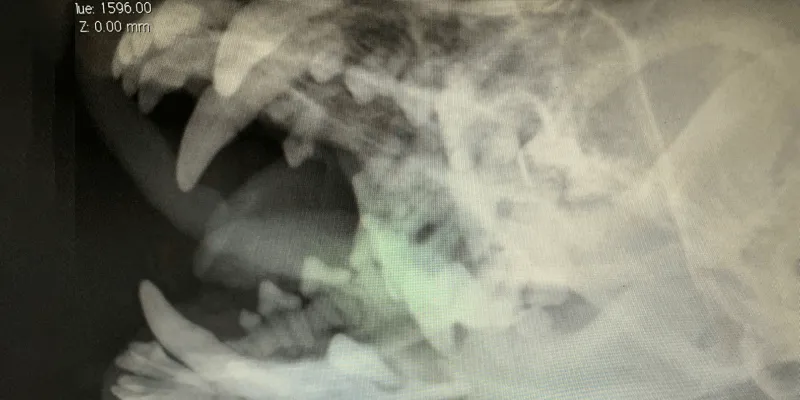

各種検査

お預かりして、レントゲン検査などの精密検査を行います。必要となる検査の種類や数により、必要な時間は異なります。